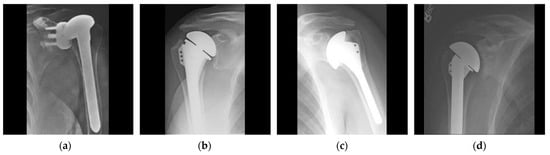

2.1. Dataset